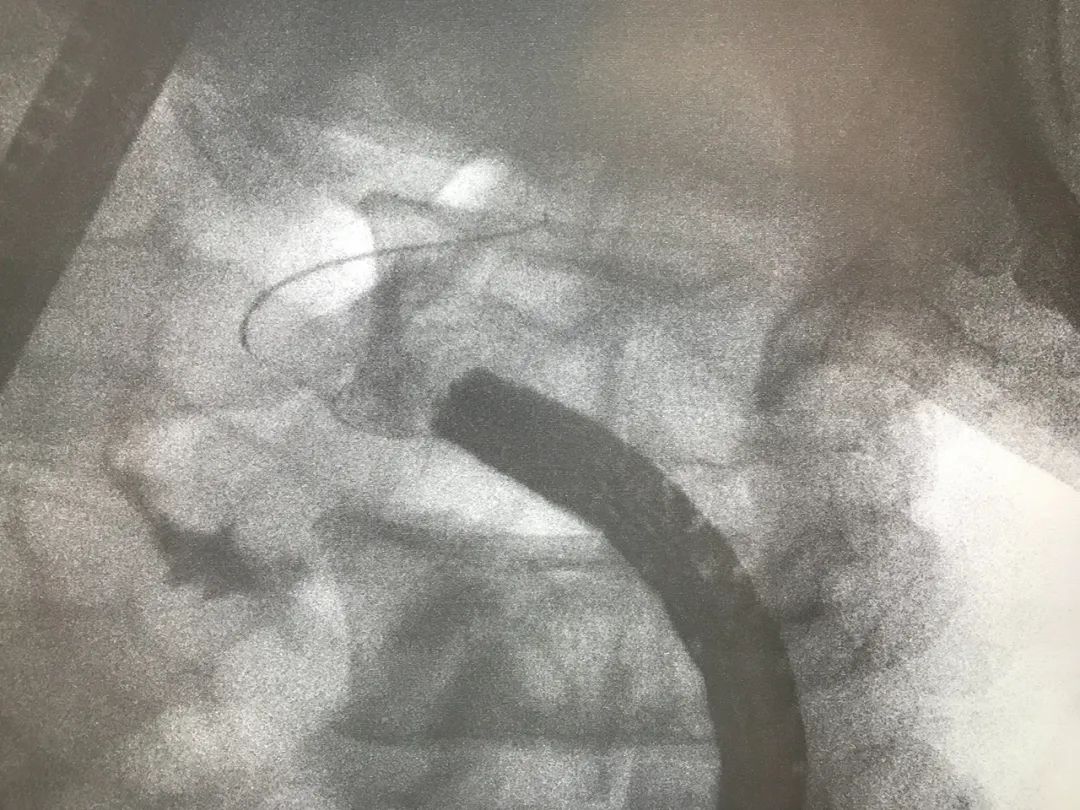

8 月 26 日,成都京东方医院普外科白文涛博士、消化内科主治医师谢宇共同为患者实施了内镜下逆行阑尾炎治疗术,该术式通过结肠镜逆行以造影导管在导丝的引导下插入阑尾腔,顺利取出阑尾腔内多个粪石,引出了脓液,解除阑尾梗阻。

内镜中心徐辉主任介绍,内镜下逆行阑尾炎治疗术是应用结肠镜经肛门到达回盲部找到阑尾开口,通过插管、造影、冲洗、引流, 达到治疗急阑尾炎的目的。